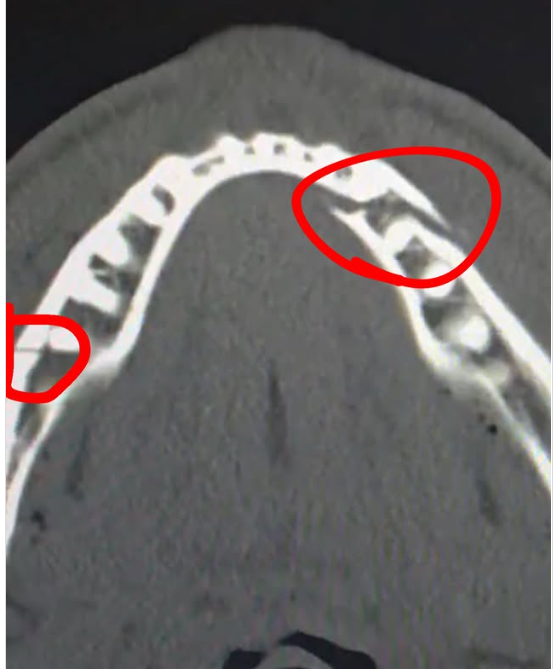

Paul je sada na društvenim mrežama objavio kakve su posljedice ovog nokauta, a na rendgenskom snimku se vidi da je njegova vilica pukla na dva mjesta. Na lijevoj strani glave je njegova vilica pretrpjela veliko napuknuće, dok je ono nešto manje na drugoj strani.

"Dvostruko slomljena vilica. Dajte mi Canela u narednih deset dana", poručio je Paul tako u šali prozvavši Canela Alvareza, legendarnog Meksikanca koji važi za jednog od najdominantnijih boksera današnjice – čovjeka poznatog po nevjerovatnoj snazi udarca, čeličnoj bradi i karijeri u kojoj je pobjeđivao svjetske prvake u više težinskih kategorija, čak i one koji su na papiru djelovali veći i jači od njega.